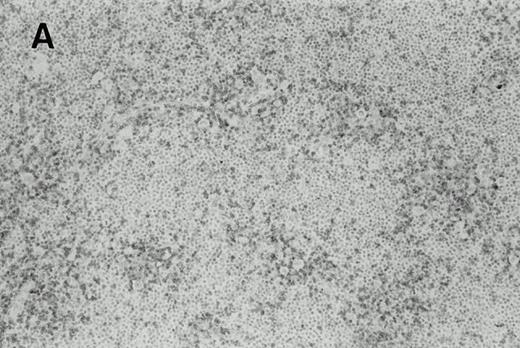

Immunohistochemistry of CD3 in case 1: (A) low (40×), (B) high (400×). CD3+ T cells are associated with clusters of H-RS cells, often forming a ring around the H-RS cells. Inset shows CD30+ H-RS cells. Immunohistochemistry of MB2 in case 2: (C) low (40×), (D) high (400×). MB2+ CLL cells are present around a nodule of HD. H-RS cells are admixed with T cells and histiocytes and only scattered MB2+ small lymphocytes are present.

The results of the immunohistochemical studies are shown in Table1 and Fig 2.The CLL cells were reactive with B-cell markers in all three cases, and also expressed CD43 in cases 2 and 3, as is commonly observed in B-CLL.23 The H-RS cells expressed CD15 and CD30 in all three cases. In case 1, a small subset of the H-RS cells also expressed CD20. The small lymphocytes forming the inflammatory background of the HD component in cases 2 and 3 were mostly T cells. Scattered B lymphocytes were also present, more prominently in case 2 where the Hodgkin's foci were less sharply demarcated from the CLL areas as compared with case 3. In case 1, although the typical cellular background of HD was absent, most of the small lymphocytes associated with the H-RS cell areas were T cells which often formed a ring around the H-RS cells.